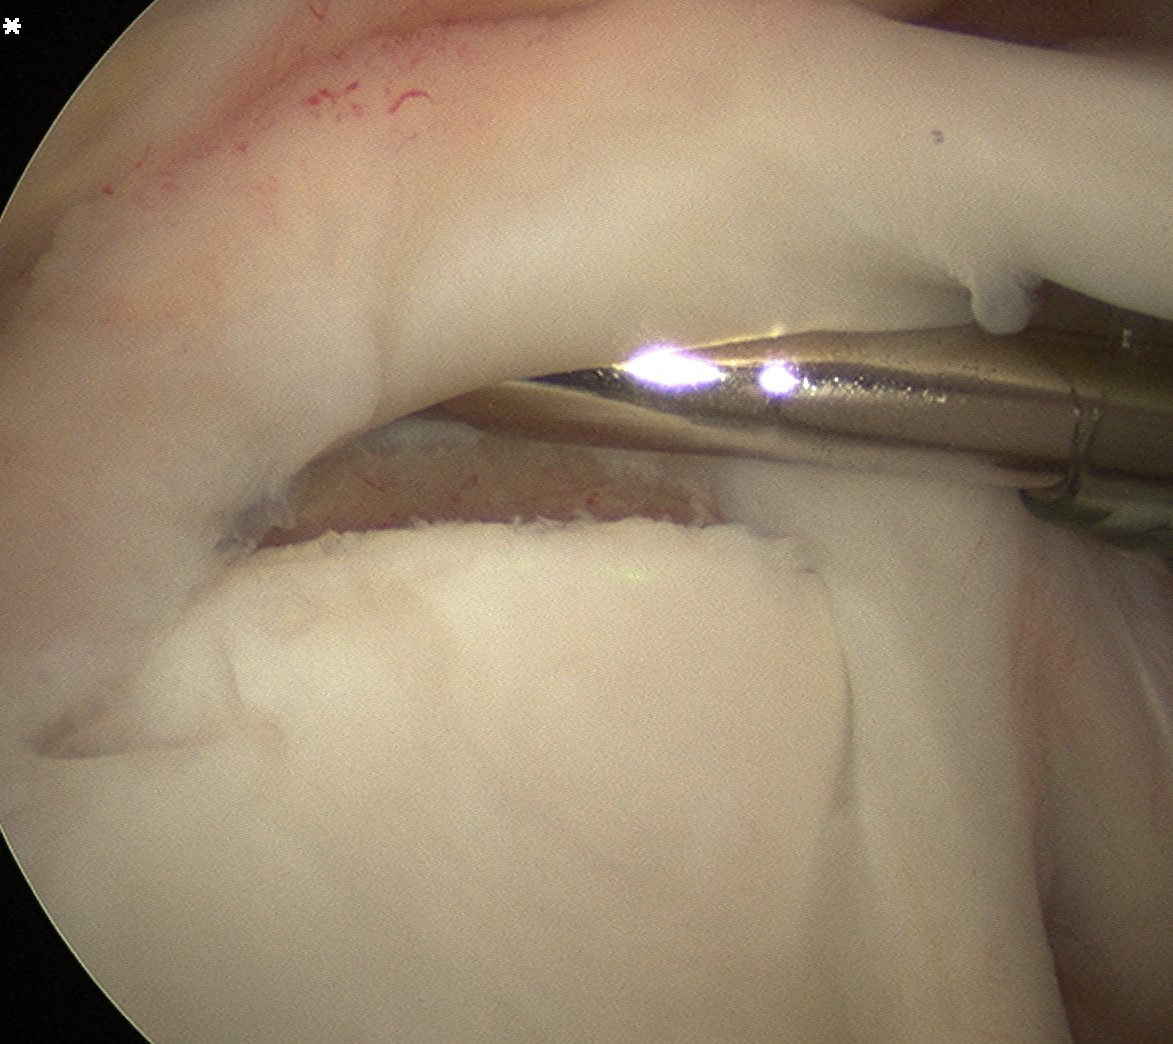

PVNS

Definition

Pigmented Villo-Nodular Synovitis

- benign inflammatory process that arises in synovial tissues

- contains significant amounts of hemosiderin